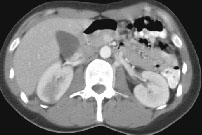

Fig.1 Fig.2 Fig.3

HELICAL CT FINDINGS: The CT was performed on AIC’s multi-slice helical CT (MSCT) scanner. Images with 5 mm collimation were obtained before, immediately following and 5-10 minutes after power injection of IV contrast. The region of the appendix was unremarkable. However, the right kidney and perinephric region were abnormal. Fig. 1 and Fig. 2 illustrate patchy and wedge-shaped low attenuation areas in the right kidney, and Fig. 3 shows stranding/infiltration of perinephric fat around the lower pole consistent with inflammatory changes (arrows).

DIAGNOSIS: The CT images are most compatible with acute pyelonephritis (APN) even without any laboratory results. Shortly after, results of blood work and urinalysis revealed leukocytosis and pyuria substantiating the CT diagnosis.